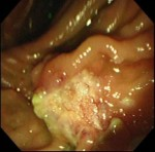

Magnified endoscopic observation using narrow-band imaging of periampullary adenoma in a patient with familial adenomatous polyposis

A 35-year-old man had undergone prophylactic colectomy for FAP 3 years earlier. On the forward-viewing and side-viewing endoscopy done for surveillance, the overlying mucosa of the major papilla showed even granularity. On magnifying duodenoscopy using a narrow-band system (NBI), which uses modified optical filters and yields clear images of fine surface structures on the mucosal layer, a compact formation of round pits was seen in the affected ampulla. The microvascular architecture on NBI magnification showed no abnormalities, such as dilated, tortuous or network-like vessels, suggestive of malignancy. On endoscopic retrograde pancreaticocholangiography there was no intraductal growth, and endoscopic ultrasonography showed confinement to the mucosal layer. The ampullary lesion was completely resected using endoscopic snare papillectomy. Histopathological examination of the removed specimen showed tubular adenoma without malignant foci. The patient's post-treatment course was uneventful and without complications, and no local recurrence was noted on repeat endoscopy.